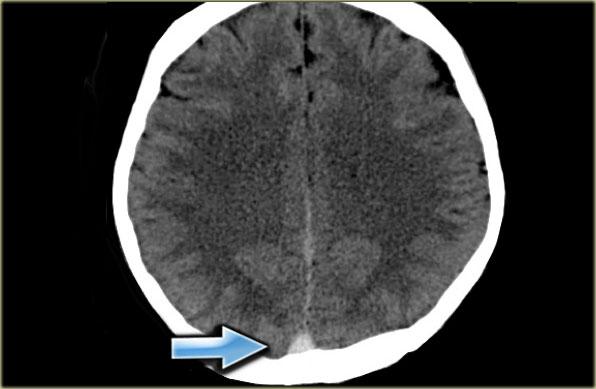

Hình ảnh bên trái cho thấy phù nề cạnh đường giữa hai bên và xuất huyết nhỏ ở bệnh nhân huyết khối xoang tĩnh mạch dọc trên.

Hình ảnh bên trái là tái tạo CT mặt phẳng đứng dọc của một bệnh nhân có xuất huyết cạnh đường giữa hai bên do huyết khối xoang tĩnh mạch dọc trên.

Mũi tên đỏ trên hình CT có tiêm thuốc cản quang chỉ khuyết thuốc do huyết khối gây ra.